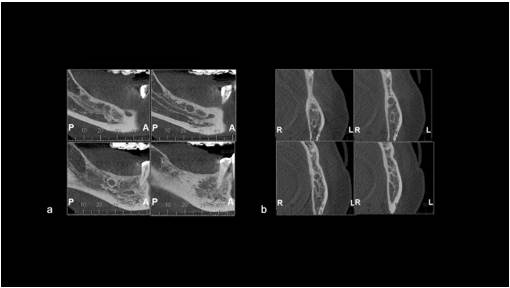

Una mujer de 60 años fue atendida en una clínica privada en mayo de 2015 para la colocación de un implante dental. Sin embargo, durante los exámenes de imagen, se detectó la presencia de una lesión en la mandíbula. En ese momento, la paciente no informó de ningún síntoma. Los exámenes extra e intraorales no revelaron hallazgos anormales (como sensibilidad, tumefacción o dolor). Su historial médico no presentaba particularidades, y no se recopiló ninguna otra información relevante de la anamnesis. La Tomografía Computarizada reveló una lesión hipodensa con margen esclerótico que medía aproximadamente 0,8 x 0,8 x 0,7 cm en la mandíbula posterior derecha (Figura 1a y 1b). Según el historial del paciente y los hallazgos clínicos, el diagnóstico clínico inicial fue de un QR. Se obtuvo el consentimiento informado y, bajo anestesia local, se realizó una biopsia excisional. El material fue enviado al Centro de Diagnóstico de Enfermedades Orales (CDEO) de la Universidad Federal de Pelotas, Brasil. La muestra macroscópica consistía en una masa de tejido blando bien delimitada, de color marrón, con una superficie regular que medía 0,5 x 0,5 x 0,2 cm. La muestra se colocó en formalina al 10% y se sometió a análisis histopatológico.

Figura 1. Tomografía computarizada inicial (TC) - mayo de 2015 - mostrando una lesión hipodensa unilocular con margen esclerótico que mide aproximadamente 0.8 x 0.8 x 0.7 cm en la mandíbula posterior derecha (a: sección sagital) (b: sección coronal).